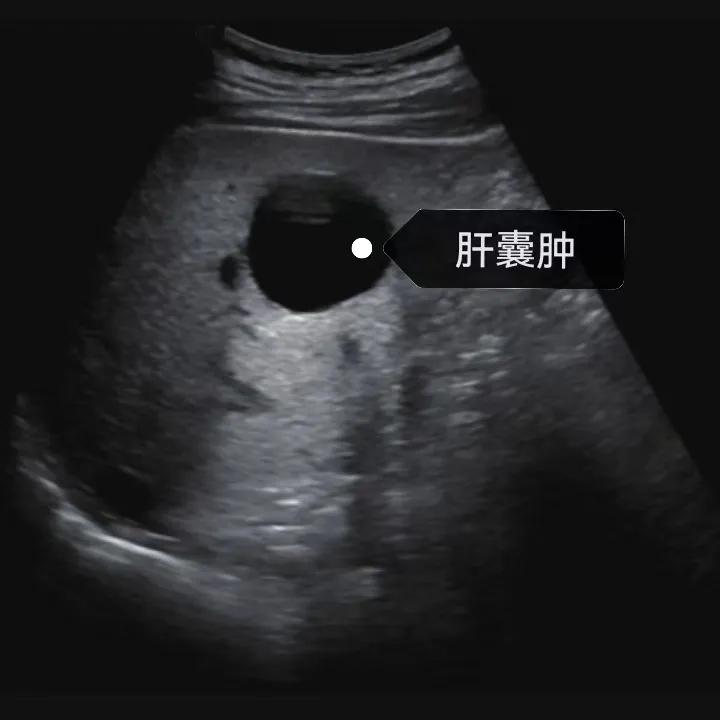

漯河市中醫(yī)院健康科普:認(rèn)識(shí)肝囊腫

隨著人們健康意識(shí)的提升,越來(lái)越多的人每年會(huì)進(jìn)行健康體檢,由于腹部(肝膽胰脾)超聲作為常規(guī)體檢項(xiàng)目之一, 肝囊腫的檢出率也愈發(fā)升高,大部分人對(duì)“腫”字都比較困惑,今天我們就來(lái)一起了解一下肝囊腫。

肝囊腫是一種常見(jiàn)的肝臟良性疾病,呈圓形或橢圓形,外由上皮細(xì)胞包裹形成包膜,內(nèi)由清亮、無(wú)色、無(wú)細(xì)胞成分的囊液填充,看上去就像是一顆注滿了水的氣球,因此通俗一點(diǎn)說(shuō)就是肝臟中的“水泡”。

超聲通常是診斷肝囊腫的首選方法,彩超對(duì)肝囊腫的檢出率可達(dá)98%,<1cm的囊腫也可檢出。肝囊腫常表現(xiàn)為圓形或橢圓形無(wú)回聲,包膜光滑完整,邊界清晰,可有側(cè)壁回聲失落征象,后方回聲增強(qiáng)。病程長(zhǎng)、囊腫較大者或囊內(nèi)有過(guò)出血、感染者,無(wú)回聲腔內(nèi)可見(jiàn)少量絮狀回聲漂浮。超聲對(duì)肝囊腫的診斷準(zhǔn)確而靈敏,且方法簡(jiǎn)單、無(wú)創(chuàng)、費(fèi)用低、可重復(fù)性高,因此常常被作為首選。